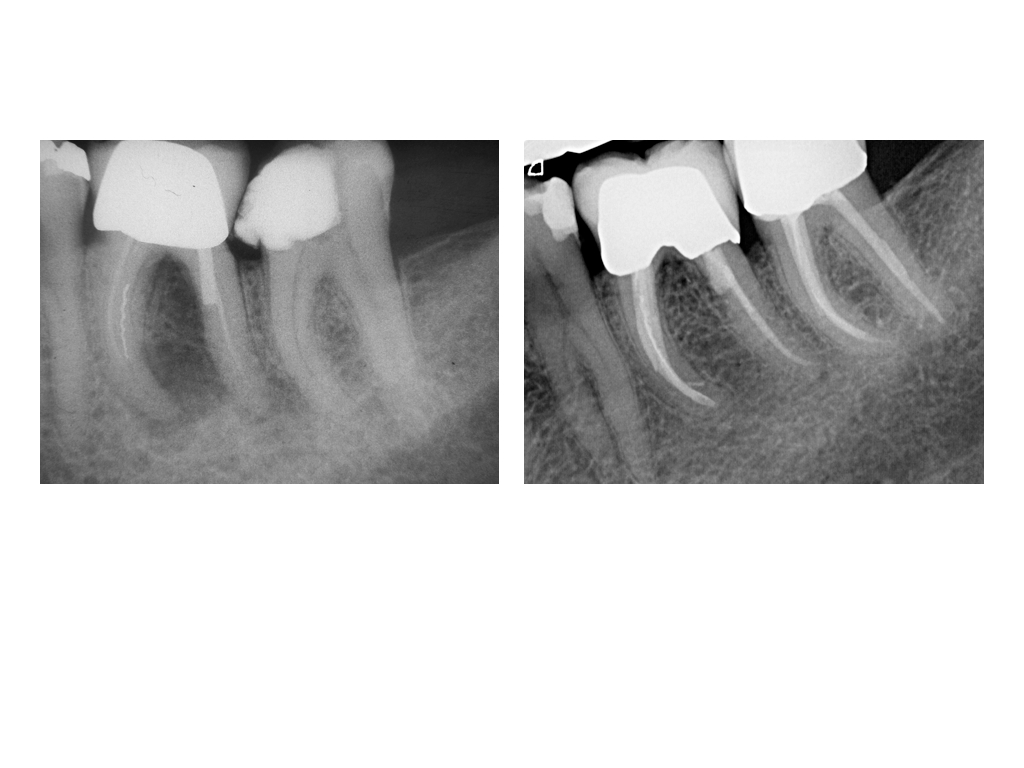

DMAWFR.017 Veröffentlicht 27. Februar 2012 am 1024 × 768 in Die Mutter aller WF – Revisionen – Recall nach 5,5 Jahren